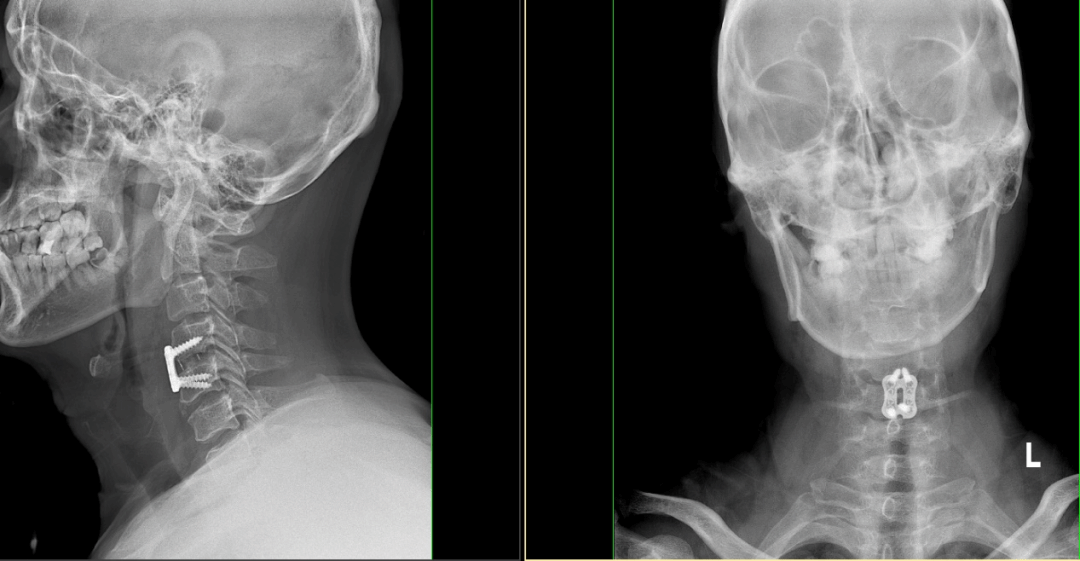

陈欣主任术前与详细评估患者病情并结合影像学资料,决定采用“显微镜下颈椎前路手术”,待与其及家属讲解手术方案及风险后,患者及家属表示同意手术。手术历经1小时余,顺利完成。手后当日患者表示颈肩部疼痛及左上肢麻木症状明显改善。

此次显微镜下颈椎前路手术的成功开展在北方院区尚属首例,与传统手术相比,显微镜下放大的手术视野,解决了传统颈椎前路手术因减压位置深,操作空间小造成的视野的问题便于助手与术者的配合,此外显微镜下操作对于致压物减压等细节处理显示十分清晰,对组织的损伤更小,手术部位感染更少,可以精确观察到椎间的静脉丛及出血位置,有效止血,同时硬膜上的微小血管,看得更加清晰,便于双极止血,有效降低术中出血,同时最大限度既降低减压过程中硬膜及脊髓的损伤,极大提高减压的安全性、有效性和精准性,利于患者快速康复。

北方院区首例显微镜下颈椎前路手术成功